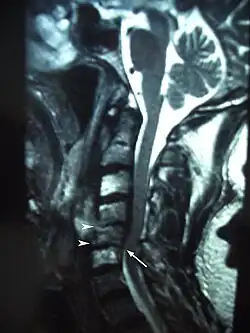

Osteoradionecrosis (ORN) is a serious complication of radiation therapy in cancer treatment where radiated bone becomes necrotic and exposed.[1] ORN occurs most commonly in the mouth during the treatment of head and neck cancer, and can arise over 5 years after radiation.[2] Common signs and symptoms include pain, difficulty chewing, trismus, mouth-to-skin fistulas and non-healing ulcers.

The pathophysiology of ORN is fairly complex and involves drastic changes to bone tissue as a result of DNA damage and cell death caused by radiation treatment.[3] Radiation therapy targeting tumor cells can affect normal cells as well,[4][5] which can result in the death of bone tissue. Advances in radiation therapy have decreased the incidence of ORN, estimated at around 2%.[6] Certain risk factors including the size and location of tumor,[7][8] history of smoking[2] or diabetes,[7] and presence of dental disease[3][9] can affect the chances of developing ORN.

Radiation therapy destroys cancer primarily by causing DNA damage that promotes cell death.[4][5] Tumor cells within a cancer are especially susceptible to damage by radiation as they frequently develop mutations in the DNA repair mechanisms that allow normal, healthy cells to recover from radiation damage.[12] However, excessive radiation doses can cause even normal cells to be overwhelmed by DNA damage and lead to local tissue changes and necrosis. Scientists have been conducting investigations into the exact mechanisms of these changes to help create treatments since osteoradionecrosis (ORN) was first described by Regaud in 1922.[13] Several competing theories have emerged over the years with resultant changes to accepted treatments. Initially, it was believed that ORN arose from a combination of radiation, trauma and infection.[14] According to this belief, radiation damage to the bone caused the bone to weaken, making it susceptible to microfractures caused by trauma and allowing bacteria to invade.[14] This theory placed ORN on a spectrum of disease with osteomyelitis, so it was primarily treated with antibiotics.[3] In 1983, Robert E. Marx, a prominent oral and maxillofacial surgeon, refuted the notion that trauma and infection were requirements in the development of ORN.[3] Marx proposed that ORN was the result of cumulative tissue damage caused by radiation, creating disturbances in cell metabolism and homeostasis that resulted in cell death and hypocellular tissues.[15] In addition, radiation causes injury to the endothelial cells of local vasculature, creating a hypovascular environment which leads to decreased oxygen delivery resulting in hypoxic tissues.[15] The decrease of vasculature helps explain why the mandible is more commonly affected than maxilla, as the mandible is served primarily by the inferior alveolar artery, whereas the maxilla is served by various arteries and has a more robust blood supply.[16] In sum, Marx believed that ORN was essentially hypocellular-hypovascular-hypoxic tissues behaved much like chronic non-healing wounds.[3][15] Initial reports by Marx and others showing that treatment with hyperbaric oxygen (HBO) prevented ORN helped support this theory.[17] However, later studies began to raise doubts about the effectiveness of HBO therapy and question whether Marx's theory was comprehensive enough to guide treatment.[18]

Current understanding is guided primarily by the work of Delanian and Lefaix, who proposed the radiation-induced fibroatrophic (RIF) process.[19] Advances in lab techniques allowed scientists to perform more detailed studies of ORN specimens. Analysis of samples showed that tissues undergoing ORN underwent three phases of disease: 1) prefibrotic, 2) constitutive organized and 3) late fibroatrophic phases.[19] During the prefibrotic phase, injury to endothelial cells secondary to radiation causes destruction of local vasculature, and recruitment of inflammatory cells and fibroblasts via pro-inflammatory cytokines like TNF-α, FGF-β and TGF-β1.[19] In addition, osteoblasts within the bone are damaged and destroyed, leading to decreased production of normal bone tissue.[3] In the constitutive organized phase, fibroblasts persist and are converted to myofibroblasts by these same cytokines, that begin to fibrous extracellular matrix (ECM) within the affected bone.[19] Consequently, the increased production of ECM by myofibroblasts coupled with decreased production of osteoid by osteoblasts results in weakened bony tissue.[19] Finally, during the late fibroatrophic phase, the affected bone becomes hypocellular as myofibroblasts begin to die and leave behind weak, fibrotic tissue.[19] Ultimately, these tissues are fragile and susceptible to damage by trauma or infection with little ability to repair or defend themselves due to the lack of vasculature caused during the pre-fibrotic phase.[19] Given this understanding of the pathophysiology of ORN, current treatments are targeted at decreasing inflammatory cytokines and reducing free radical damage to DNA.[19][20]